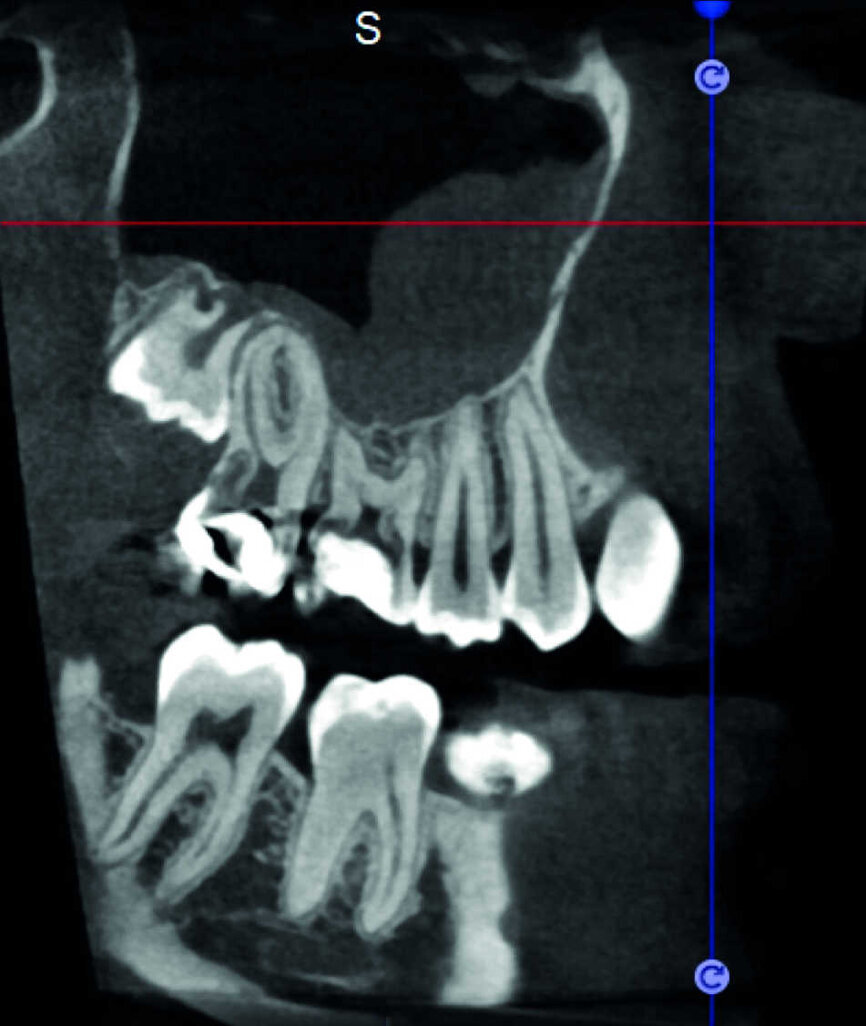

Le cas avec lequel je souhaite commencer mon exposé clinique est un exemple parfait de la difficulté à définir l’origine des symptômes d’un patient, par l’examen d’une simple radiographie intraorale. Non seulement l’examen 2D ne permet pas d’établir avec certitude la présence d’une lésion, mais surtout, il est impossible d’en déterminer la taille, la morphologie et le type. Au contraire, une analyse de l’imagerie 3D offre une image claire de la situation clinique. Chez ce patient, les coupes coronales et sagittales révèlent la présence d’une importante lésion s’étendant de l’apex de la racine mésiale de cette molaire jusqu’à la zone de furcation, tandis que les coupes axiales nous permettent d’analyser précisément l’anatomie endodontique et, en particulier, la forme de la racine mésiale, qui apparaît fusionnée avec la racine palatine. Un panorama complet du cas peut donc guider le processus de décision et orienter le plan de traitement vers une modalité bien précise de traitement (Figs. 1–4).